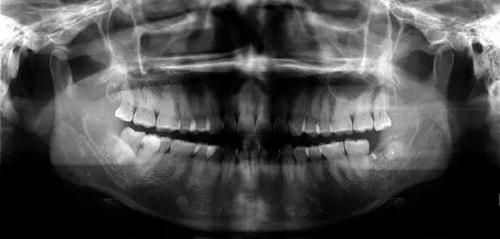

下邊也是一個斷根病例

遇到斷根怎么辦?我的觀點:拔!但有個前提,必須保證安全,否則寧可保留,因此拔牙前的溝通很重要!